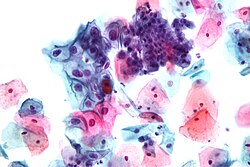

Od uzetog uzorka radi se citološki razmaz, koji se fiksira na mikroskopskoj pločici i boji po Papanikolauovoj metodi. Poslije bojenja vrši se mikroskopska analiza morfoloških osobina stanica, kojom se mogu otkriti znaci zapaljenja grlića, uzročnici infekcije, dobroćudne i zloćudne stanice i druge patohistološke promjene.